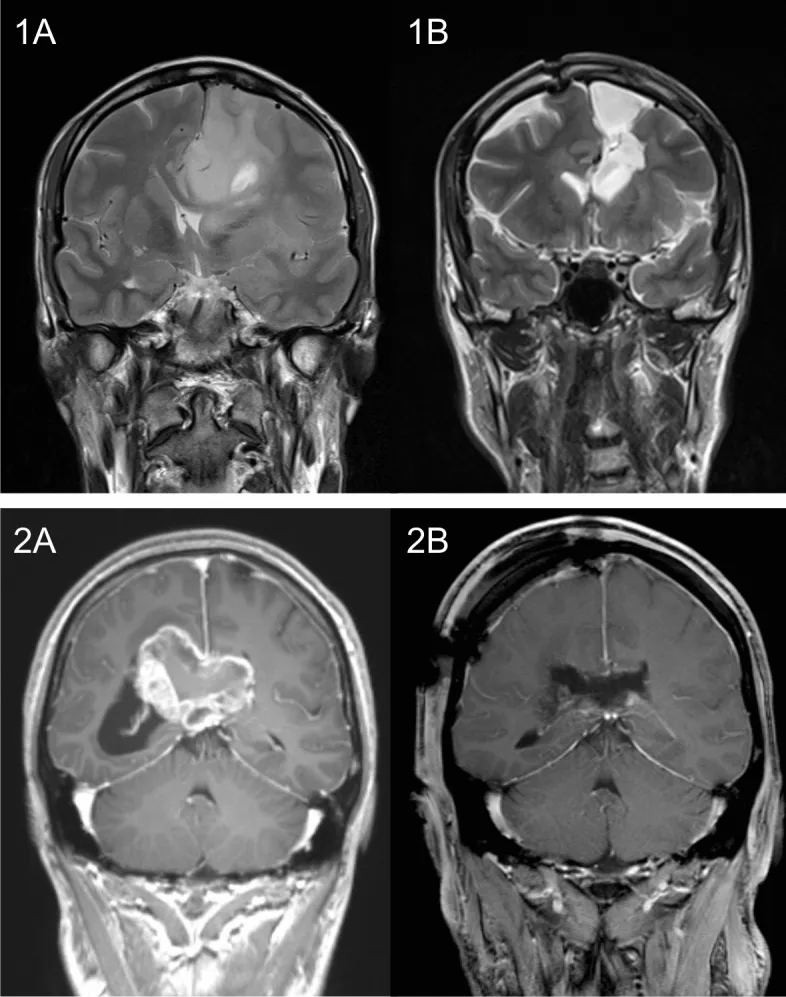

两例胼胝体侵犯性胶质母细胞瘤患者治疗情况:患者1为36岁男性,接受巨大左额叶胶质母细胞瘤次全切除术,后续行同步放化疗。该患者在任一观察时间点均未出现任何严重认知功能障碍。患者2为38岁男性,接受侵犯胼胝体压部主体的巨大胶质母细胞瘤次全切除术。术前存在严重记忆障碍,术后逐渐改善;术后新出现的轻度注意力及语言功能障碍亦随恢复逐步好转。